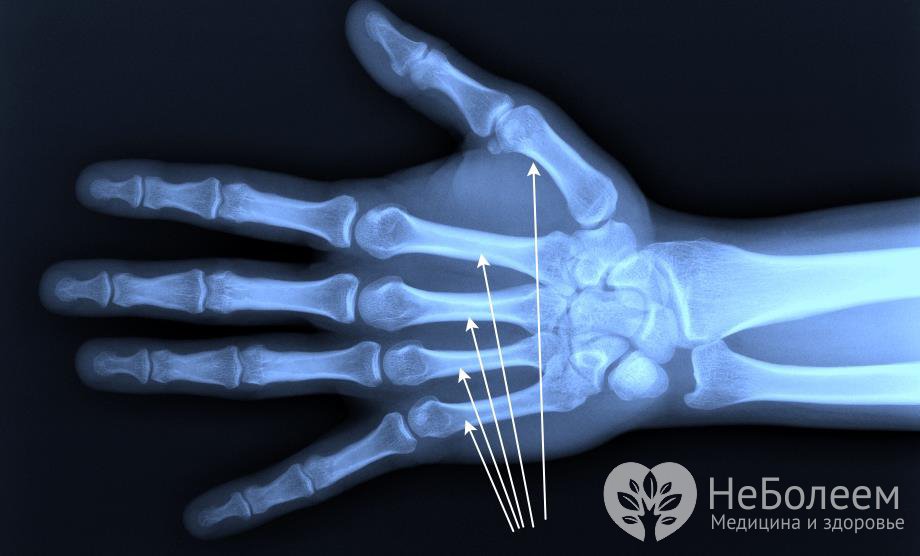

Пястная кость представляет собой короткую трубчатую кость, расположенную на кисти и отходящую от запястья в виде луча. У человека на каждой руке по пять пястных костей. Каждая кость состоит из основания, тела и головки. Эти кости соединяются суставами с костями запястья и основанием первой фаланги пальцев руки.

Пястные кости отсчитываются от большого пальца руки и имеют изогнутую форму к кисти. В каждой такой кости есть тело и эпифиз. Тело пястной кости имеет три поверхности – заднюю, медиальную и боковую. Медиальная и боковая поверхности разделяются гребешком, где находится отверстие, проходящее в питательный канал.

Тело пястной кости вогнуто в тыльную сторону, а боковые поверхности основания представляют собой суставные площадки, которые соединяют смежные кости. Суставные поверхности имеют седловидную форму.

Основание третьей пястной кости имеет отросток шиловидного типа. Внизу дистальной части располагается головка пястной кости шаровидной формы. Боковые поверхности головки пястной кости шероховатые.

Каждую головку пястной кости и ее тело можно прощупывать через кожу на поверхности кисти. Между пястными костями есть межкостные промежутки, которые называются пястями.